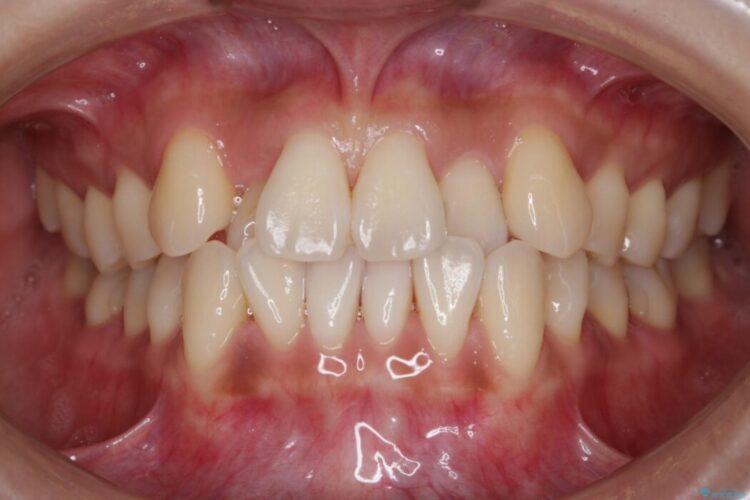

前歯のガタガタを気にされて来院されました。

検査の結果、骨の厚みに余裕がないことが判明しましたので、幅の拡大と歯の側面を削るIPRでは歯周病に対する不安を拭いきれないと判断しました。

よってマイクロインプラントを用い、奥歯から順番に遠心移動させることによってスペースを確保することにしました。